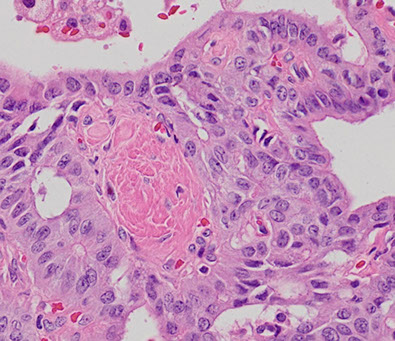

NIFTP

Figure 3 (a) NIFTP often demonstrates microfollicles intercalating between attenuated larger follicles as seen here in this encapsulated tumor. Inset—diagnostic nuclear features are more common in microfollicular areas. (b) NIFTP also frequently shows accentuation of nuclear features at the periphery, as evidenced by the paler appearance at low-power magnification. Inset—the periphery demonstrates readily visible diagnostic nuclear features. In both insets, the nuclear features are not as prominent as commonly seen in classic papillary

thyroid carcinoma  [2]